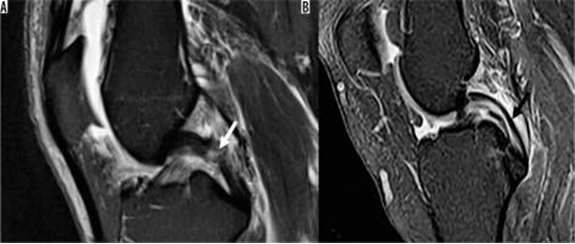

Hình 7. Vết rách ngang sụn. Hình ảnh pd coronal xóa mỡ với tín hiệu tuyến tính trong sụn (mũi tên đóng) kéo dài đến mặt dưới của thân sụn bên, phù hợp với vết rách. Tín hiệu cao (mũi tên mở) ở mặt ngoài, mặt sụn giữa không kéo dài đến bề mặt tạo hình sụn và phù hợp với thoái hóa niêm mạc.

Hình 8. Nước mắt tay cầm xô lệch. A và B là hình ảnh cộng hưởng từ pd xóa mỡ với vết rách tay cầm cho thấy một mảnh sụn dịch chuyển liền kề với dây chằng chéo sau (mũi tên trắng), được gọi là dấu hiệu "dây chằng chéo sau đôi ", cũng như một mảnh sụn bị dịch chuyển trong rãnh liên chất (mũi tên đen). C là hình ảnh pd xóa mỡ với vết rách ở tay cầm cho thấy mảnh bị dịch chuyển ra phía trước (mũi tên trắng), tiếp giáp với sừng trước, được gọi là dấu hiệu "sừng trước kép".